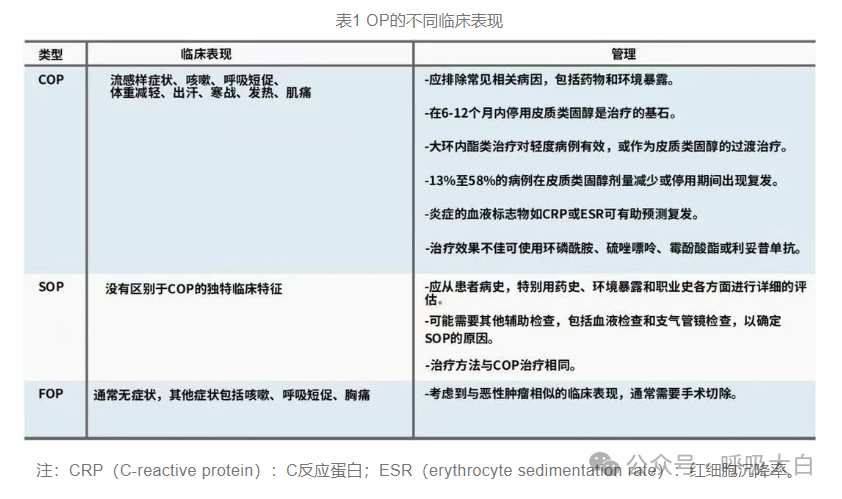

临床分型

局灶性机化性肺炎

局灶性机化性肺炎相对少见(见于<15%的COP患者),患者常无症状。单发病灶通常可通过 手术切除治愈。局灶性机化性肺炎必须与肺癌鉴别。

暴发性疾病

1.部分机化性肺炎患者表现为快速进展的临床病程(例如,需高流量吸氧和机械通气)。

2.在这种情况下,必须排除继发原因,特别是感染、结缔组织病、自身免疫病、药物或环境物 质暴露、弥漫性肺泡损伤或间质性肺疾病急性加重。

3.排除感染后,建议静脉给予糖皮质激素治疗。

4.呼吸衰竭是死亡的主要原因,通常发生在住院后30~50日。

瘢痕机化性肺炎

在一些机化性肺炎病例中,气腔充满松散的纤维黏液样结缔组织,伴有腔内致密嗜酸性纤维化 形成,肺基础结构保留。肺实质可见线状纤维带和化生骨形成区。瘢痕变异型似乎预示着纤维化 非特异性间质性肺炎,这是一种更顽固的机化性肺炎,应该从形态学上与典型COP鉴别。

急性纤维素性机化性肺炎

急性纤维素性机化性肺炎是一种罕见的肺泡填充性疾病,其特征是斑片状分布。这种变异型可 为特发性,也可与其他病程(如弥漫性肺泡损伤、过敏性肺炎、感染、药物毒性、嗜酸性肺炎 和结缔组织病)相关。